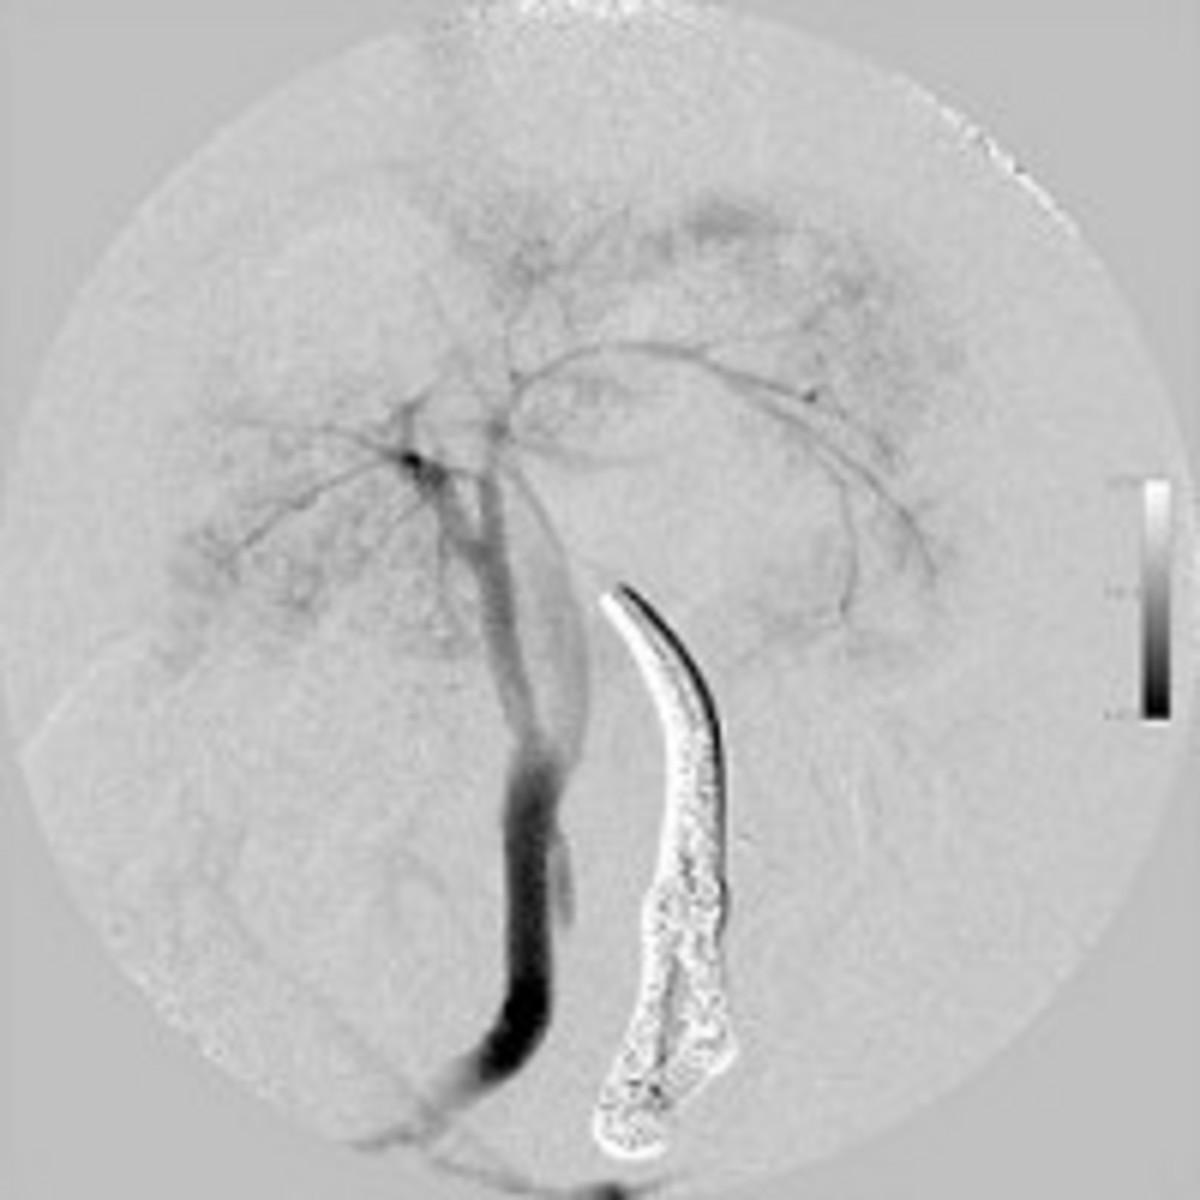

症例に全身麻酔を施した後、上腹部を正中切開し、腸間膜静脈にカニュレーション後、門脈圧の測定および門脈造影(図3)を行いました。シャント血管を同定し(図4)、仮結紮後に門脈圧測定および門脈造影(図5)を実施したところ、門脈圧の上昇が認められたため、門脈圧が過度に上昇しない程度に部分結紮にとどめ、手術を終了しました。手術時間は約60分でした。これらの手術中、約20分おきに血糖値をモニタリングしました(図6)。手術開始20分後で血糖値が158 mg/dlに上昇していましたので、グルコースの流量を0.1 g/kg/hrに減量しました。手術開始後40分では136 mg/kg/dlでしたので、この流量のまま手術終了まで維持しました。手術終了後も血糖値をモニターしながら、輸液中のグルコース濃度を調節して維持しました(図7)。

図5 仮結紮後の門脈造影像(DSA)肝内門脈枝の発達が悪い